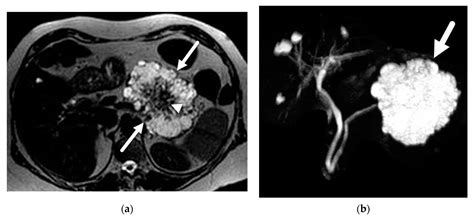

Radiologists utilize CT scans because they can detect subtle density changes within the organ. By using intravenous contrast dye—a material that highlights blood vessels and soft tissues—the scan can clearly distinguish between the healthy pancreatic tissue, potential lesions, and surrounding structures like the bile ducts, gallbladder, and major blood vessels.

• Density and Texture: Normal pancreatic tissue has a specific density. Areas that appear brighter or darker than the surrounding tissue—known as hypoattenuating or hyperattenuating lesions—often warrant further investigation.

• Ductal Dilation: The pancreatic duct, which carries enzymes to the intestines, should ideally remain narrow. If this duct is dilated, it could suggest a blockage caused by stones, scarring, or a mass.